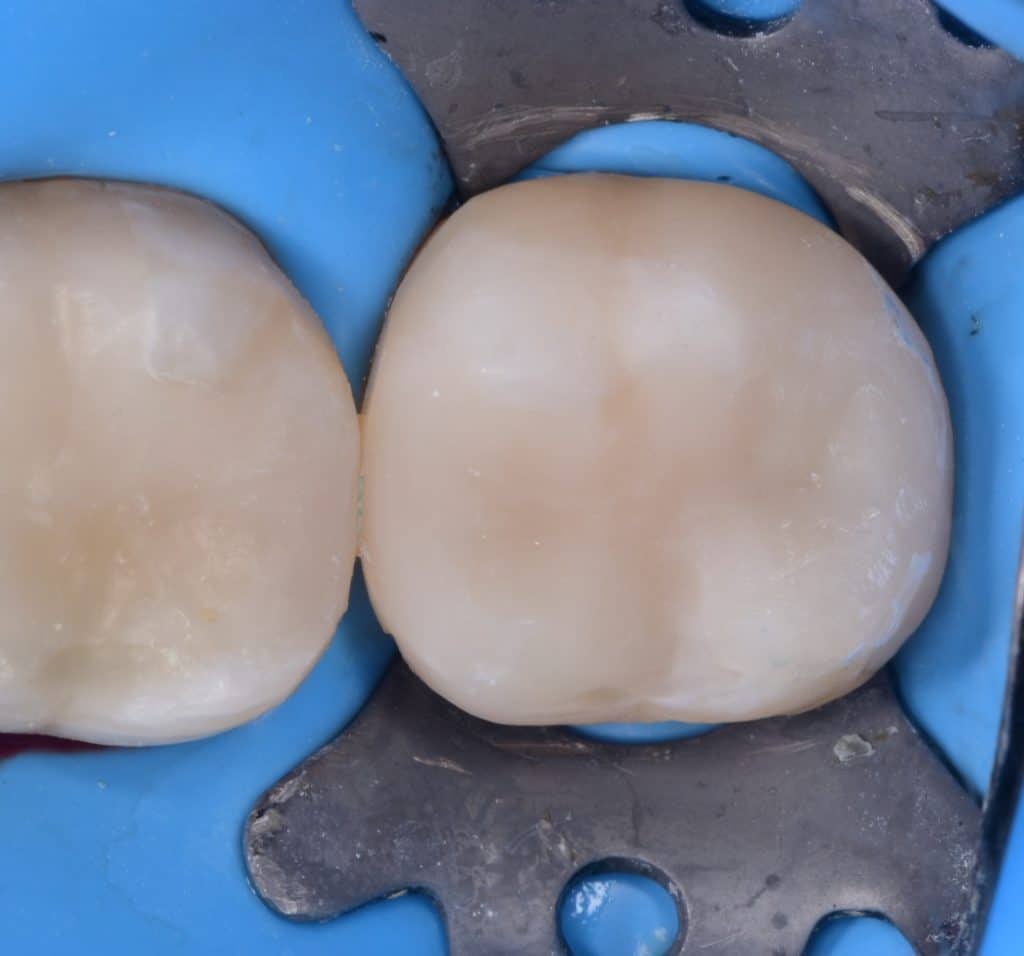

Final cavity design

Saddle metal band

IDS with G2 bond

RC with flowable composite from GC, ever x flow for dentim replacement